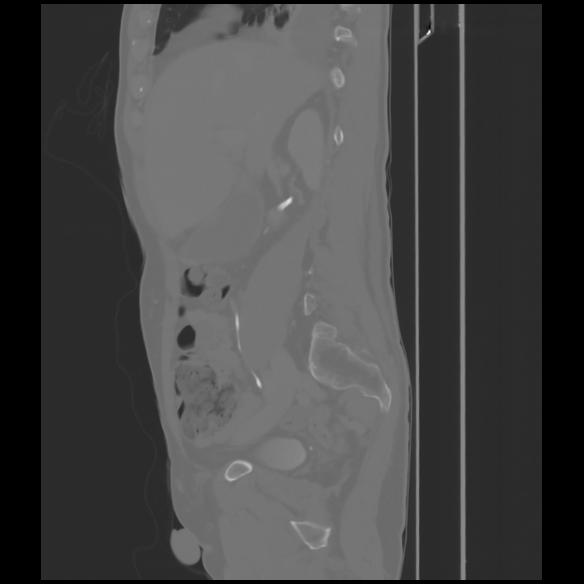

7 CUERPO,CE,Sagittal,3.000,CUERPO,Sagittal,